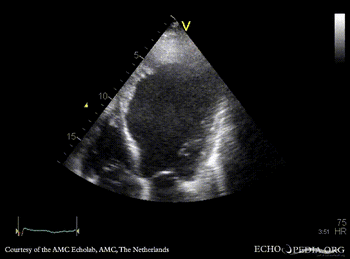

E00221.gif

A2CH: cardiac aneurysm